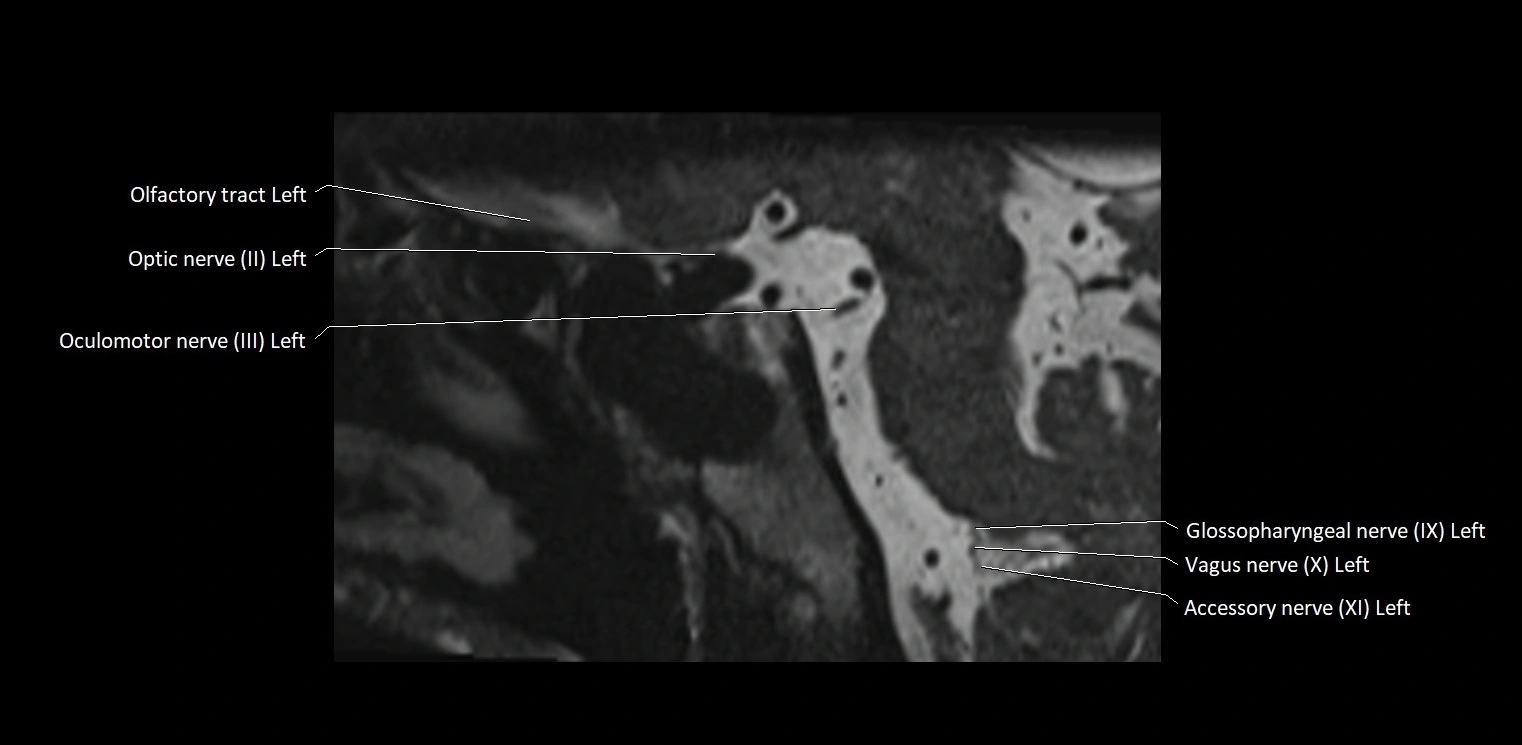

MRI images

image